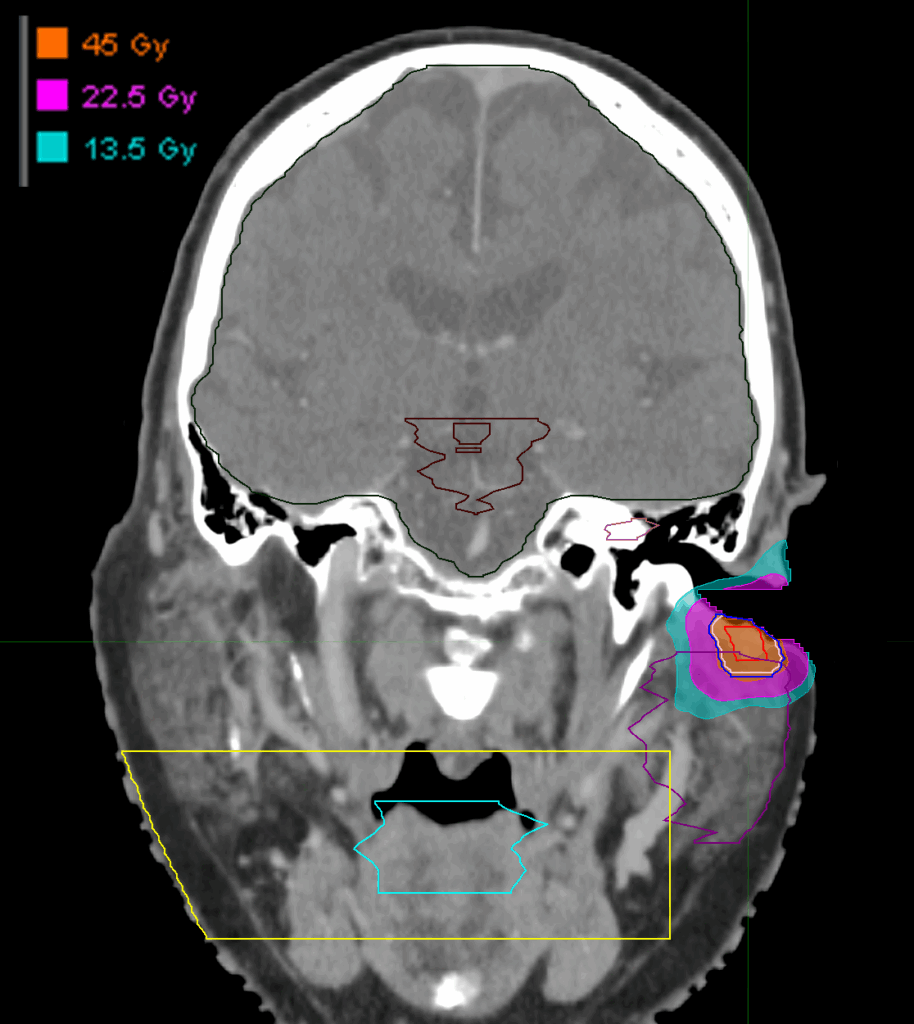

Treatment Plan Images

Dose Distributions

- Prescription to the

83% isodose line - Max. dose 54.35 Gy